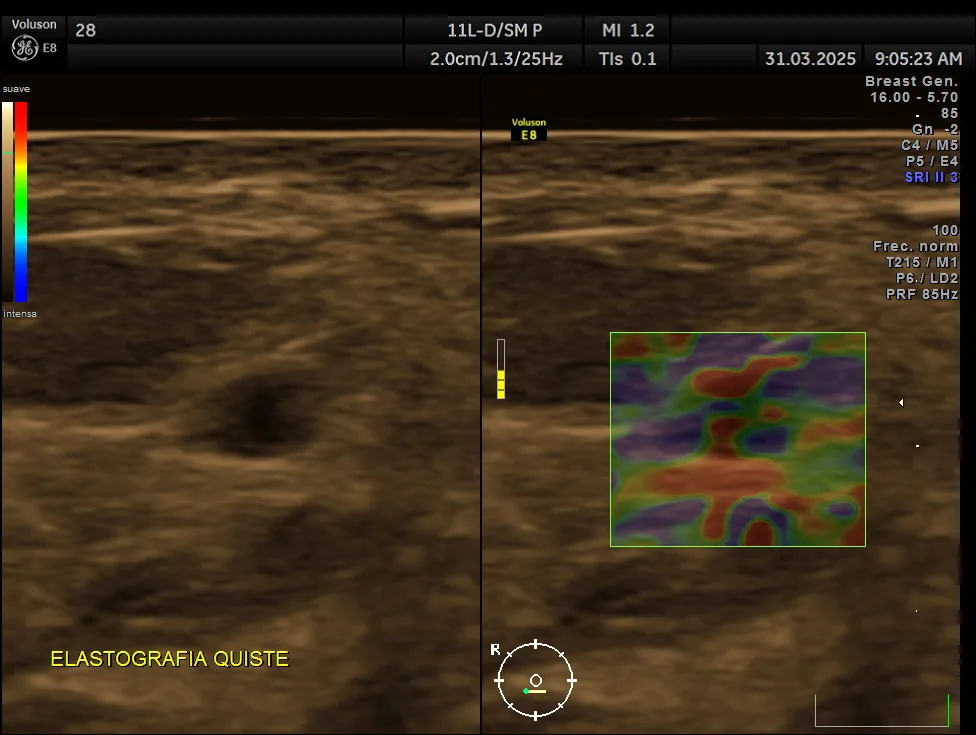

¿Qué es la elastografía mamaria y por qué es importante?

La elastografía mamaria es una tecnología avanzada que complementa la ecografía tradicional al evaluar la elasticidad y rigidez del tejido mamario. Esta herramienta resulta especialmente útil para diferenciar entre lesiones benignas y malignas, ya que los tumores suelen ser más rígidos que el tejido sano.

La ecografía mamaria muestra la estructura del tejido; la elastografía evalúa la rigidez, ayudando a diferenciar lesiones benignas y malignas con mayor precisión.